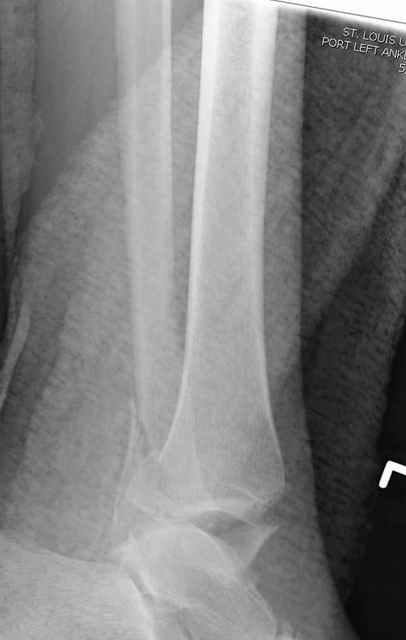

Я вот все в толк не возьму смысл отдельной фиксации малоберцовой кости пластинкой, если все равно будет аппарат с фиксацией стопы, т.е. возможностью провести спицы в пятку, таран, наружную лодыжку и еще черт-те куда. Остеосинтез пластинкой выглядит логичным в случае, когда наружная фиксация планируется как временная. Но тут-то аппарат будет окончательным фиксатором.

Еще, кстати, о фиксации лодыжки, если уж непременно хочется ее отдельно стабилизировать - при таком характере перелома замечательно должен сработать предложенный проф. Лазаревым с соратниками способ фиксации напряженной V-образной спицей. Опять же, открытая репозиция не нужна, мы делаем непрямую репозицию именно аппаратом. В приложении пример, там перелом малоберцовой куда менее поперечный, чем в данном случае, но все равно получилось закрыто без пластинки.

I can't realize why plate fibula separately if anyway external fixator including the foot is planned, i.e. one may insert wires to the talus, calcaneus, lateral malleolus and anywhere else. Plating looks reasonable if only temporary ex-fix is planned, but in the case it will be definitive.

A propos fibular fixation if one is eager to stabilize it separately. In the fracture pattern a way of closed fixation by V-shaped stressed wire (advanced by colleagues from Moscow, prof. Lazarev A.F. et al.) must be excellent. We use indirect closed reduction by the external fixator. Example attached, that fibular fracture is even more suitable for plating but the wire did the job.